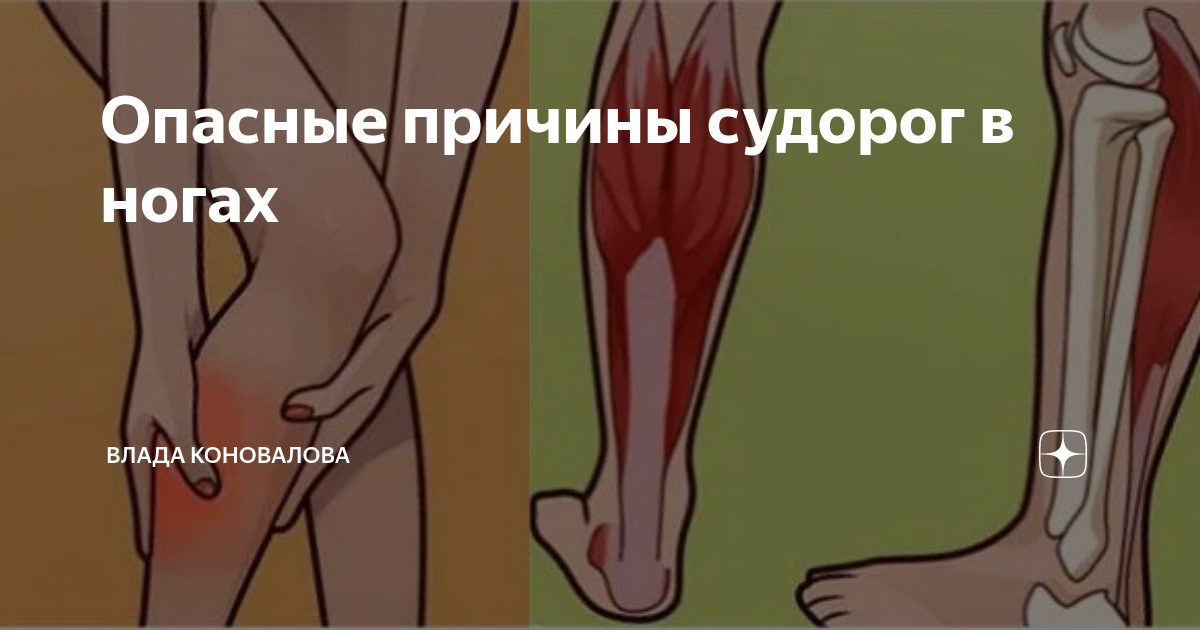

Причины судорог в ногах и способы их устранения